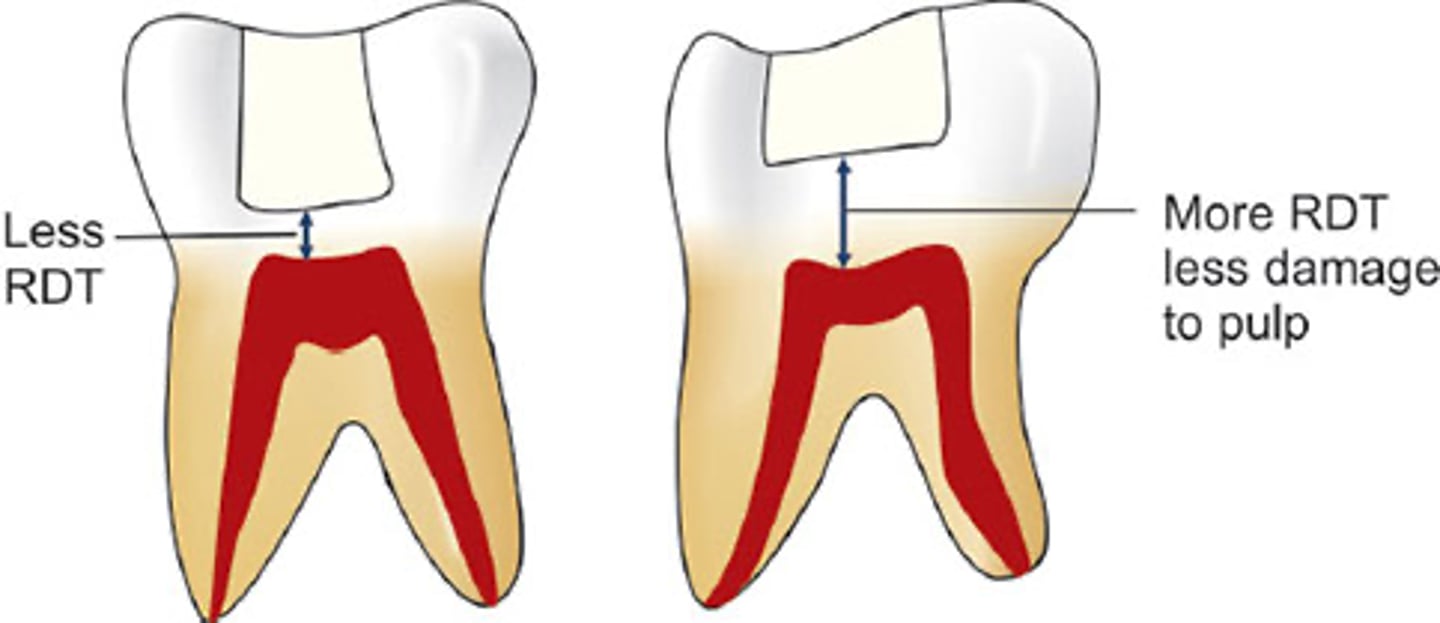

- Amount of tooth structure you have from the depth of cavity prep to the pulp

- single most important factor in protecting the pulp from insult/damage

- the pulp is MOST safe if there is at LEAST 0.5-2mm of structure btw prep & pulp

What is the Remaining Dentinal Thickness?

Remaining Dentinal Thickness (RDT)

Goes from the depth of the cavity preparation to the pulp

is the single most important factor in protecting the pulp from insult/damage

Single most important factor in protecting the pulp from insult/damage

0.5

2.0

RDT is the single most important factor in pulpal protection:

____ mm thickness of dentin protects pulp by 75%

1.0 mm thickness of dentin protects pulp by 90%

Little pulpal reaction occurs when there is an RDT of ____

mm or more!!!